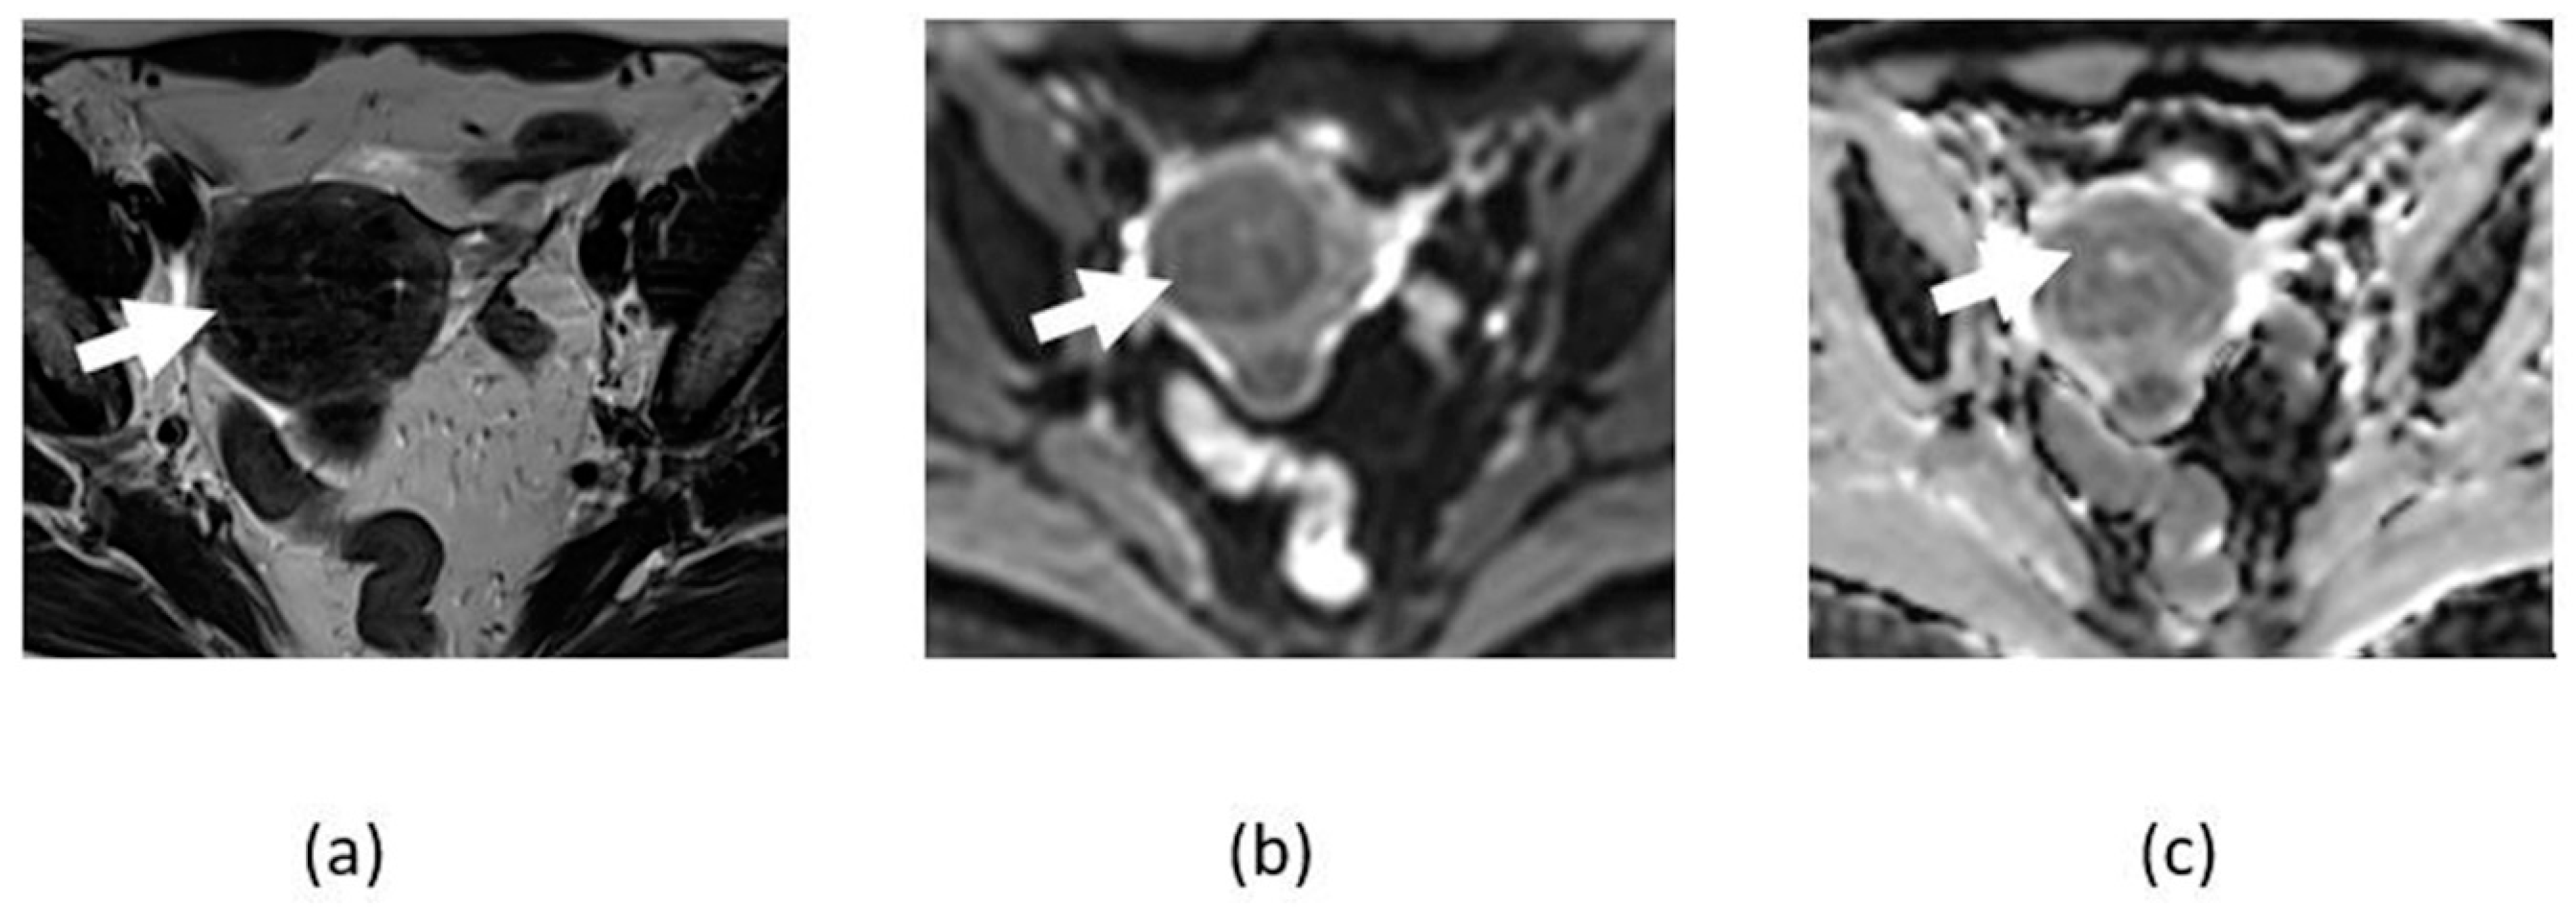

3.2. Adnexal Torsion